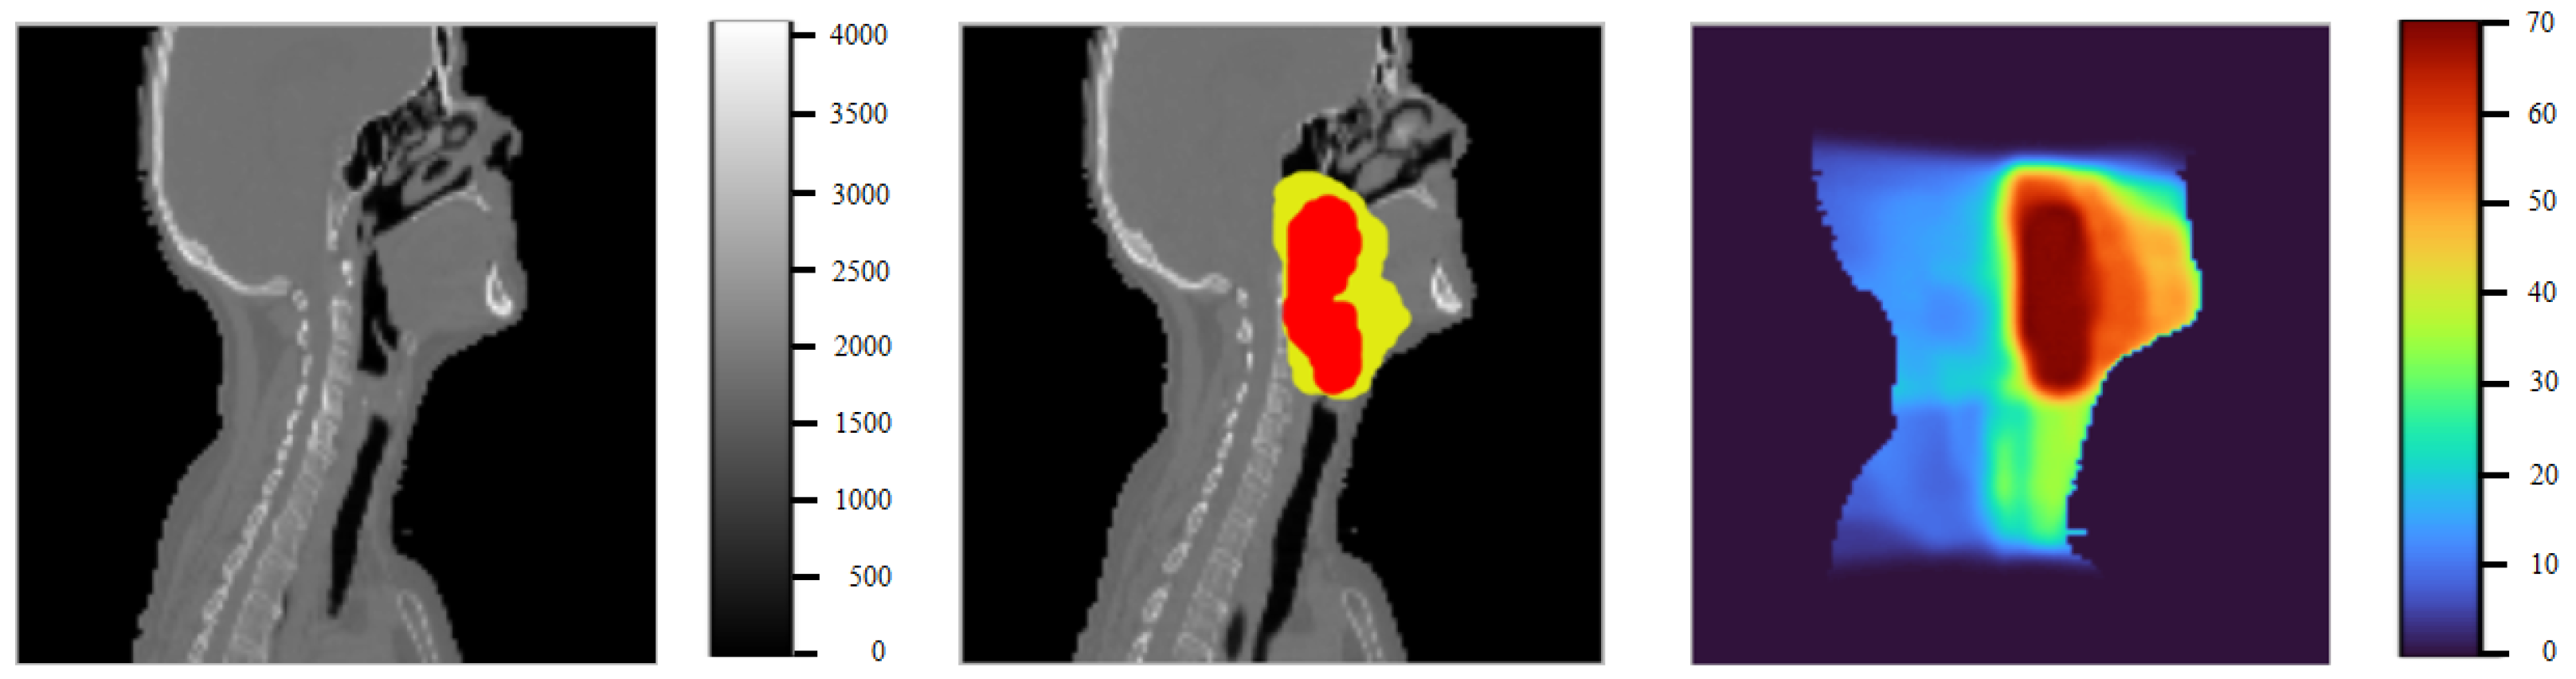

5. Results